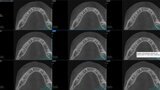

Fig.2a: Pre-op CBCT images of tooth #46: No obturation material in the distal and mesiobuccal canal (a); scanty obturation of the canals and breach of the floor of the pulp chamber, no obturation beyond a few millimetres down the orifice (b & c); radiolucency in the furcation area and periapical region of both roots (d -g).

Fig.2b: Pre-op CBCT images of tooth #46: No obturation material in the distal and mesiobuccal canal (a); scanty obturation of the canals and breach of the floor of the pulp chamber, no obturation beyond a few millimetres down the orifice (b & c); radiolucency in the furcation area and periapical region of both roots (d -g).

Fig.2c: Pre-op CBCT images of tooth #46: No obturation material in the distal and mesiobuccal canal (a); scanty obturation of the canals and breach of the floor of the pulp chamber, no obturation beyond a few millimetres down the orifice (b & c); radiolucency in the furcation area and periapical region of both roots (d -g).

Fig.2d: Pre-op CBCT images of tooth #46: No obturation material in the distal and mesiobuccal canal (a); scanty obturation of the canals and breach of the floor of the pulp chamber, no obturation beyond a few millimetres down the orifice (b & c); radiolucency in the furcation area and periapical region of both roots (d -g).

Fig.2e: Pre-op CBCT images of tooth #46: No obturation material in the distal and mesiobuccal canal (a); scanty obturation of the canals and breach of the floor of the pulp chamber, no obturation beyond a few millimetres down the orifice (b & c); radiolucency in the furcation area and periapical region of both roots (d -g).

Fig.2f: Pre-op CBCT images of tooth #46: No obturation material in the distal and mesiobuccal canal (a); scanty obturation of the canals and breach of the floor of the pulp chamber, no obturation beyond a few millimetres down the orifice (b & c); radiolucency in the furcation area and periapical region of both roots (d -g).

Fig.2g: Pre-op CBCT images of tooth #46: No obturation material in the distal and mesiobuccal canal (a); scanty obturation of the canals and breach of the floor of the pulp chamber, no obturation beyond a few millimetres down the orifice (b & c); radiolucency in the furcation area and periapical region of both roots (d -g).